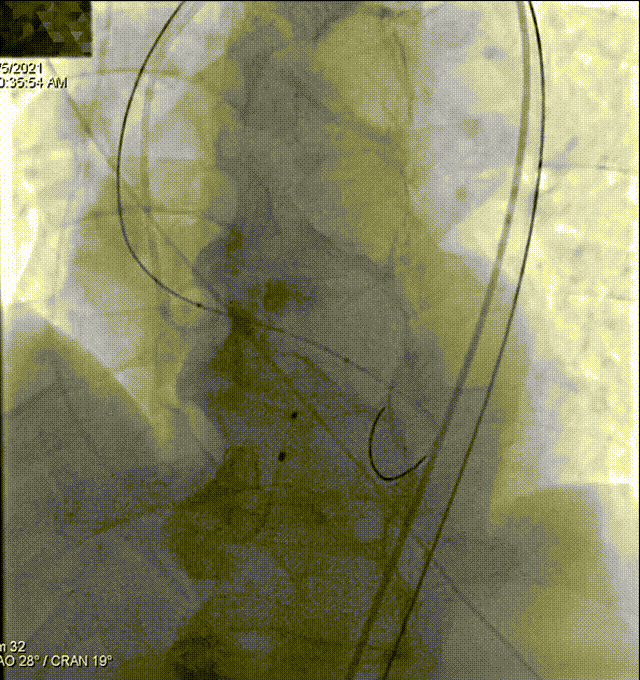

主动脉根部造影

Lunderquist导丝垮瓣

快速起搏下球囊预扩

瓣膜过弓、跨瓣

冒烟确认到达预期位置